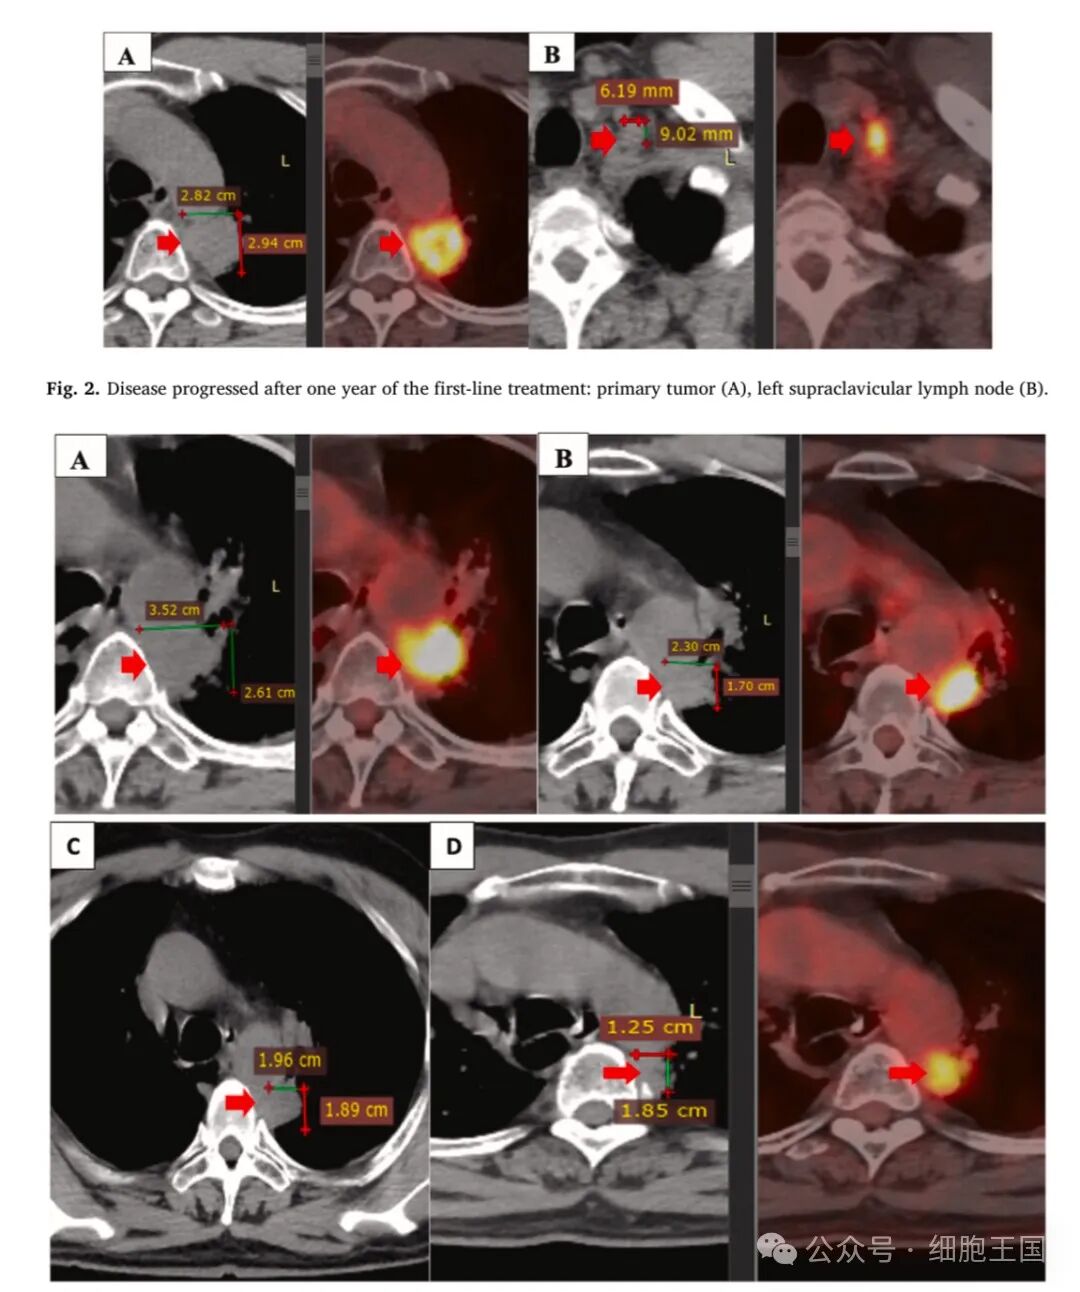

然而,2020年5月,疾病局部进展。PET/CT扫描显示原发肿瘤大小为28×29毫米(图2A),最大标准化摄取值(SUVmax)为11.2,粘连于纵隔胸膜和主动脉。此外,左侧锁骨上淋巴结出现9×6毫米的结节(图2B),左侧肺门处出现几个小结节,大小均小于10毫米。

图2:联合治疗前后的原发肿瘤变化

患者在4.5个月内共接受了6次自体NK细胞输注,每3周一次(图4)。在此期间,患者还接受了吉西他滨(1800毫克)在第1天和第8天(每3周2个周期)以及贝伐单抗(400毫克,每3周2个周期)的联合治疗。经过4.5个月的联合治疗,患者的干咳和胸痛症状消失,食欲改善,生活质量显著提高(图5)。在联合治疗期间没有观察到显著副作用,肝肾功能检测结果均在正常范围内图6)。2021年3月和9月的PET/CT扫描显示原发肿瘤大小显著缩小(图3B, 3D),纵隔和锁骨上淋巴结也未见异常。